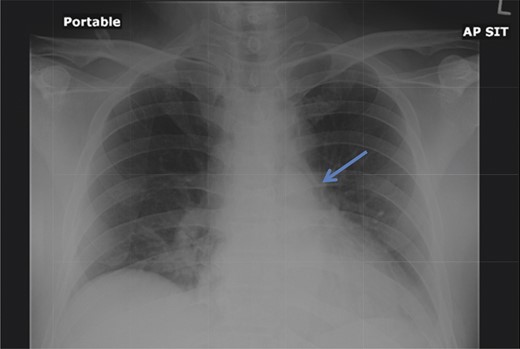

A 42-year-old male with a past medical history of hypertension was admitted for an elective TEP repair of his left inguinal hernia. Endotracheal intubation and general anesthesia were given uneventfully. The extraperitoneal space was developed with a balloon space maker, and insufflation of carbon dioxide at a maximum pressure of 12 mmHg was performed. Intraoperatively, a large incarcerated indirect left inguinal hernia containing omentum was reduced. A Optilene mesh (10 × 12 cm) was placed and tacked appropriately after hernia reduction. There were no obvious tears in the peritoneum and the total operative time was ∼90 min. No elevation of end-tidal CO2 was noted during the surgery and the patient was extubated successfully. The patient subsequently complained of left-sided chest pain on the same night of the surgery. He did not have abdominal pain. He had subcutaneous crepitus extending from the left groin to the left chest. His cardiac enzymes were negative and his electrocardiography revealed a sinus rhythm with no acute ischemic changes. A plain radiograph of the chest showed a sliver of lucency in the mediastinum suspicious for pneumomediastinum, with no obvious pneumoperitoneum or pneumothorax seen (Fig. 1). Computed tomographic (CT) imaging of the thorax and abdomen confirmed the radiograph finding of pneumomediastinum and diffuse subcutaneous emphysema tracking along the abdominal muscles bilaterally, as well as a small amount of free air and stranding in the left posterior pararenal space (Figs 2–4). The patient was treated conservatively with oral analgesia and supplemental oxygen. His chest pain resolved by the third postoperative day and he was discharged well. He was advised to avoid air travel for 1 month. He was reviewed in clinic at the 1-week and 1-month intervals and did not report any further chest pain or respiratory symptoms. His operation site healed well and he remained recurrence free.

Chest radiograph demonstrates a pneumomediastinum (arrowhead).